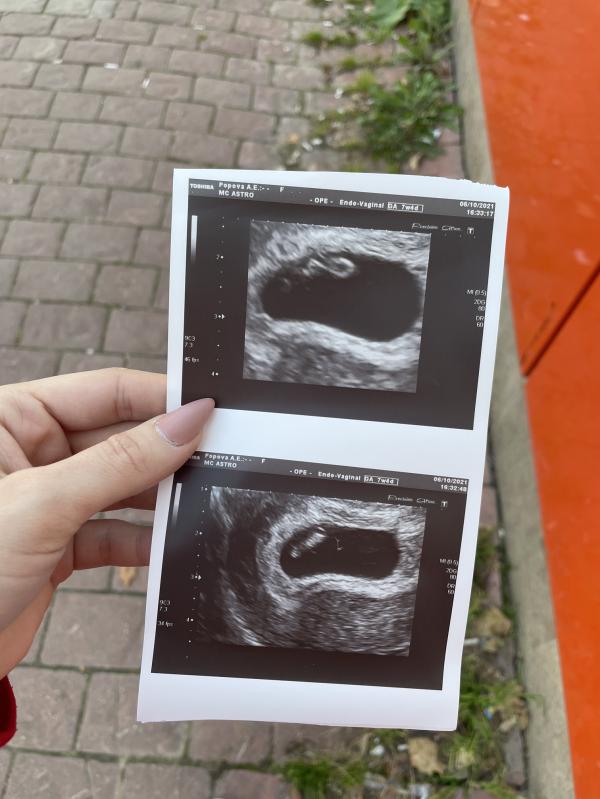

Позже была на УЗИ и узнала, что все хорошо ☺️

Услышала сердечко, чуть не расплакалась🥺🥺 это очень мило и трогательно 😭

Срок 7 недель и 1 день🥰